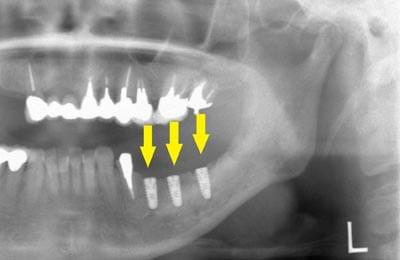

さらに、CTで、別な方向から見ると、黄色矢印のように骨が吸収されていて、緑色矢印で示される神経の通る管に迫り、インプラントが埋入できるような骨量はありませんでした。

インプラントを埋入するために、骨を増やす方法はいくつかありましたが、この場合、患者様ご自身の骨をブロック状で移植するのが最も適していると判断し、自家骨移植術を行ないました。患者様ご自身の下顎前歯の下方から骨を採取して、骨がなかった部位に移植し、スクリューで固定したCT画像です。黄色矢印部分が、2つの骨片を移植して、固定したところです。